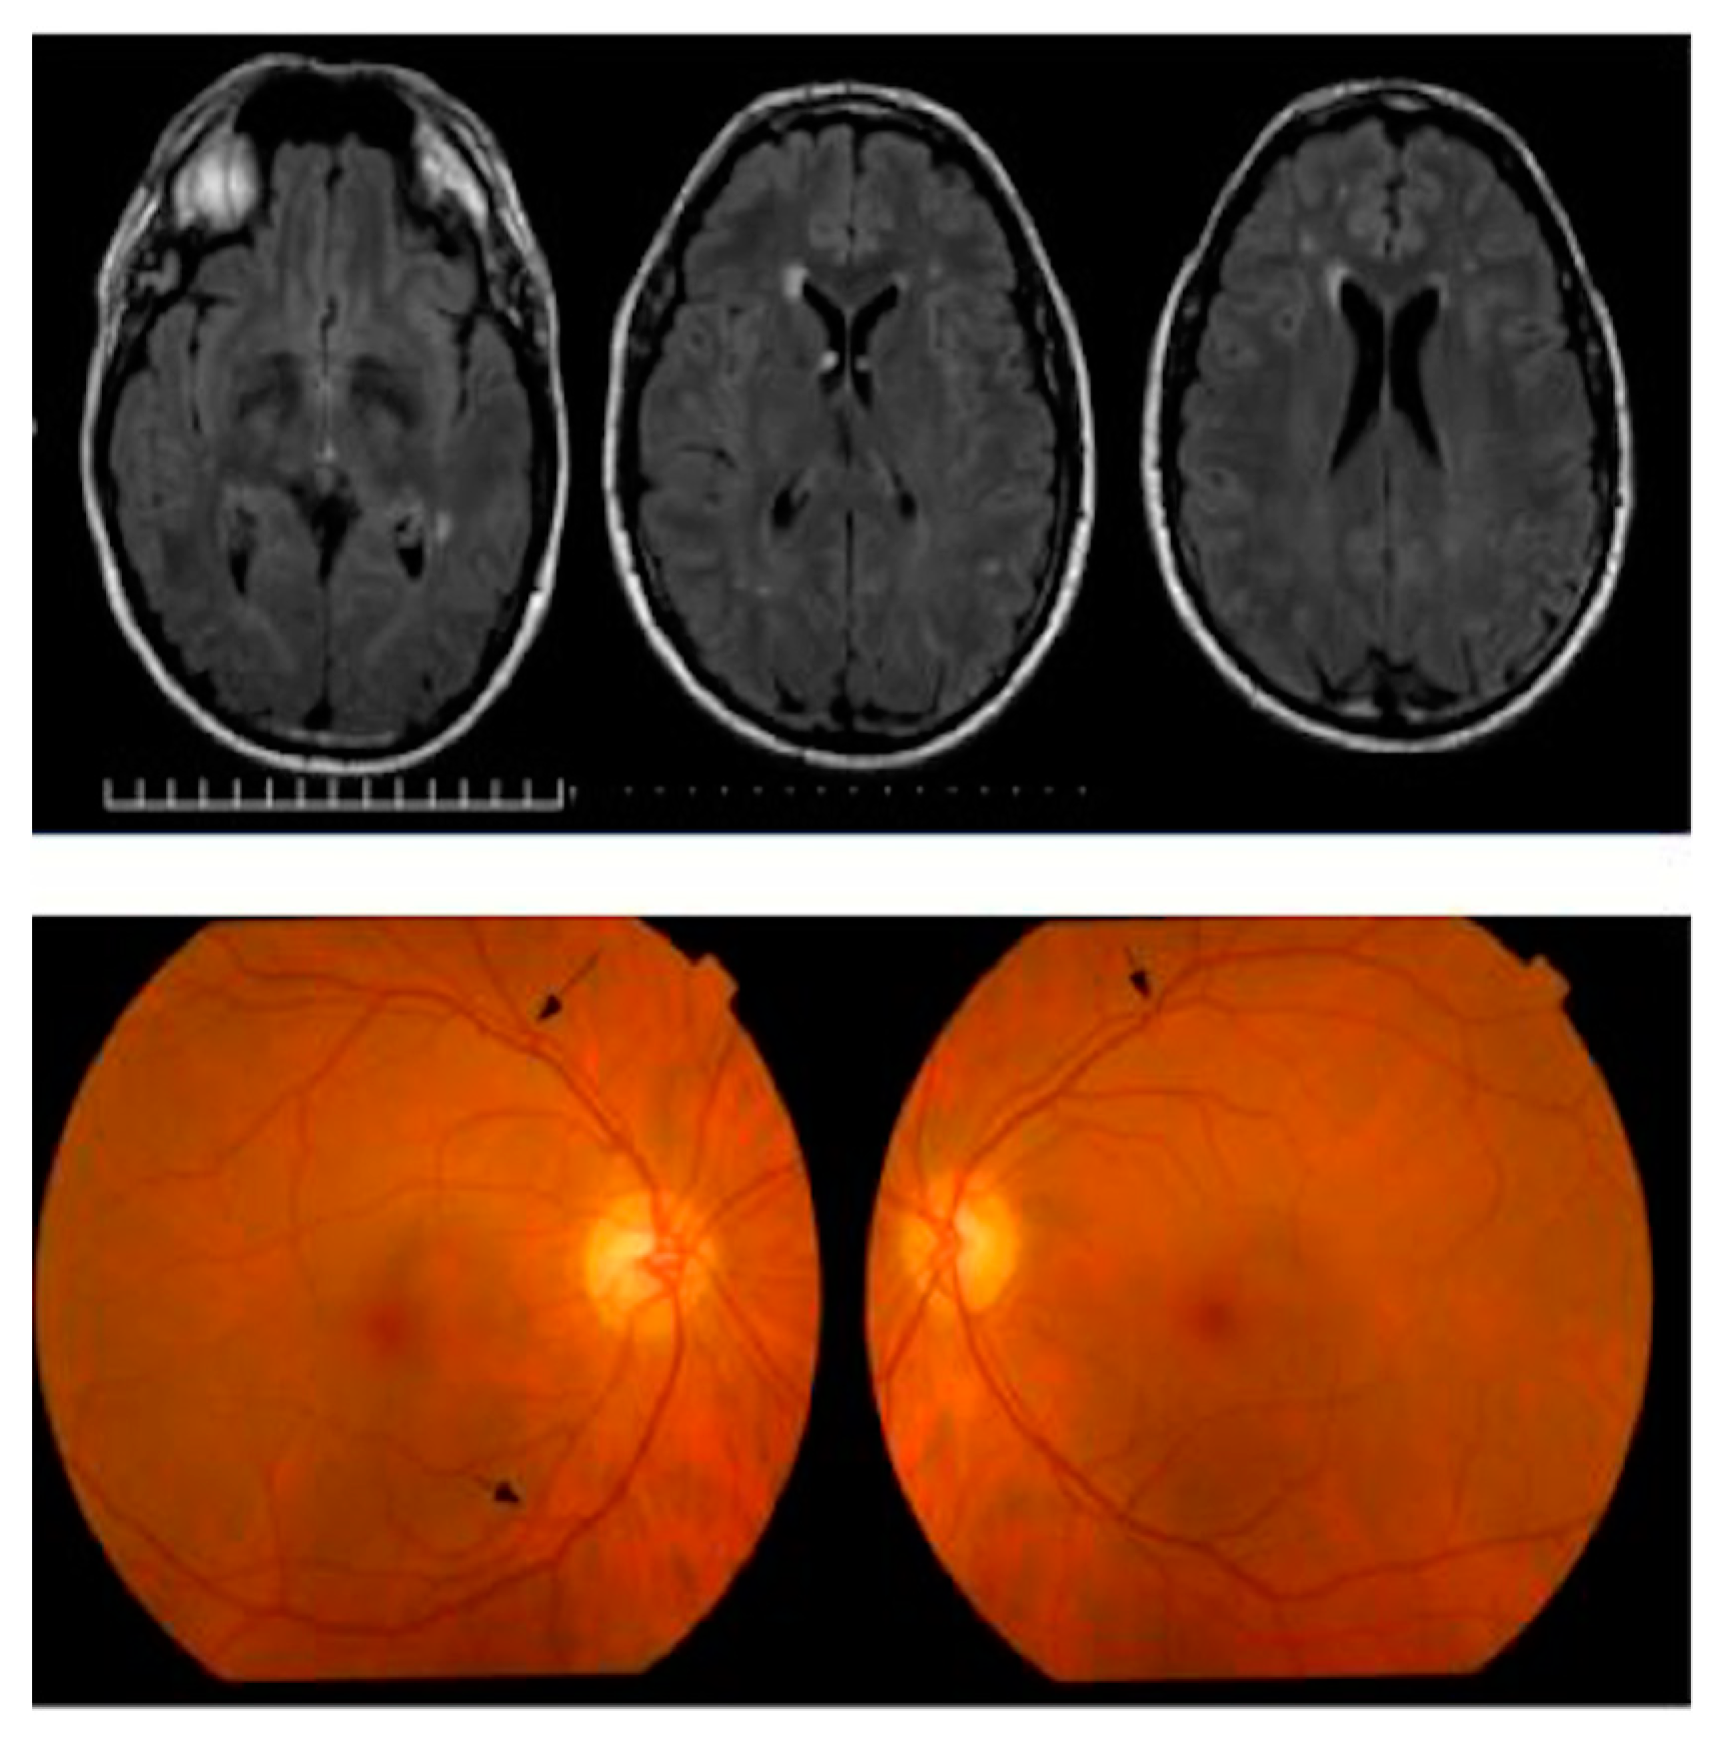

- La Morgia, C.; Ross-Cisneros, F.N.; Koronyo, Y.; Hannibal, J.; Gallassi, R.; Cantalupo, G.; Sambati, L.; Pan, B.X.; Tozer, K.R.; Barboni, P.; et al. Melanopsin retinal ganglion cell loss in Alzheimer disease. Ann. Neurol. 2016, 79, 90–109. [Google Scholar] [CrossRef] [PubMed]